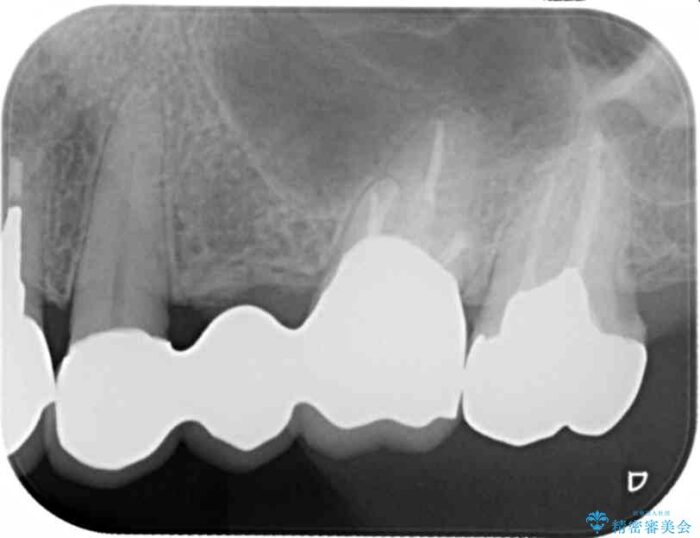

銀歯をジルコニアセラミックへと換えることで、審美性・清掃性の高い仕上がりを目指します。

ブリッジに審美的でないイメージやあまり良くないイメージをお持ちの方を多々お見受けしますが、適切な設計とすることで、見た目に自然で審美的なブリッジ治療を行うことができます。